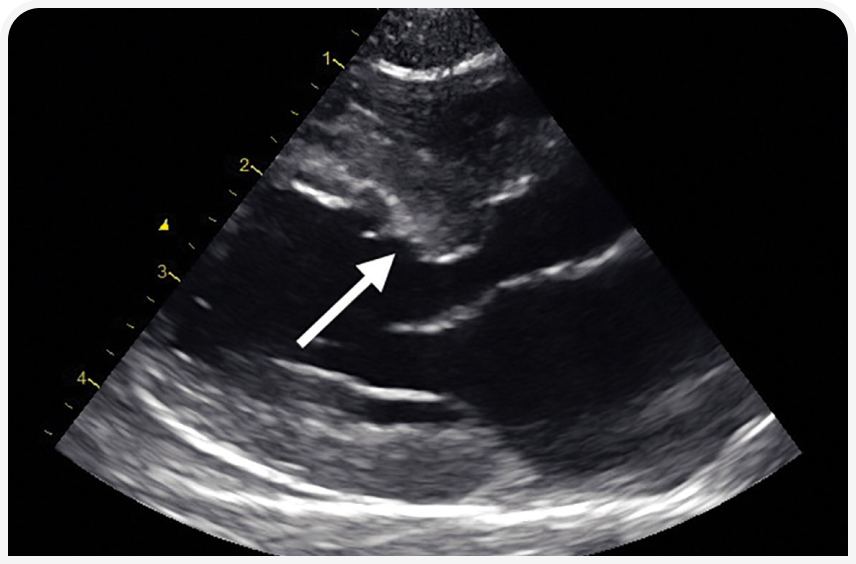

Сердце при гипертензии является органом-мишенью как у кошек (12), так и у собак (13). Вызванное системной гипертензией хроническое увеличение постнагрузки приводит к компенсаторной гипертрофии миокарда, развивающейся для нормализации напряжения стенки сердца.

У собак чаще наблюдаются диффузная и симметричная концентрическая гипертрофия левого желудочка, расширение проксимальной луковицы аорты и аортальная недостаточность, в то время как у кошек выявляемые при эхокардиографии изменения сердца включают концентрическую гипертрофию стенки левого желудочка и межжелудочковой перегородки, гипертрофию перегородки в субаортальной области (Рисунок 3) и расширение проксимальной аорты. При клиническом обследовании выявление ритма галопа, аритмии или любого шума позволяет с высокой степенью вероятности подозревать поражение сердца, но для подтверждения диагноза необходимы дополнительные исследования, такие как рентгенография органов грудной клетки, электрокардиография и эхокардиография.